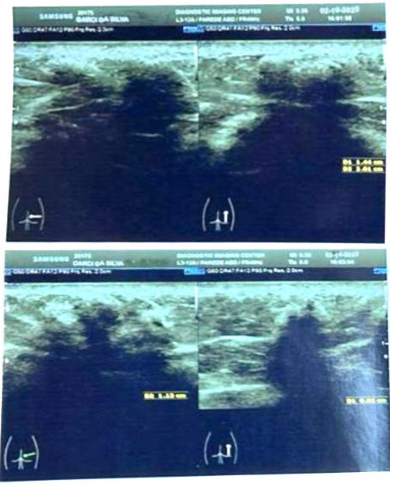

A patient who had undergone gluteal bioplasty with PMMA administered intramuscularly was selected. A subcutaneous PMMA nodule was confirmed by imaging (ultrasound) in the left lateral gluteal region (figure 1). The patient was placed in the prone position, and tumescent local anesthesia technique was used to administer 2% lidocaine with vasoconstrictor around and inside the nodule (figure 2).

Figure 1: Dermatological ultrasound imaging of PMMA nodules in the subcutaneous tissue.